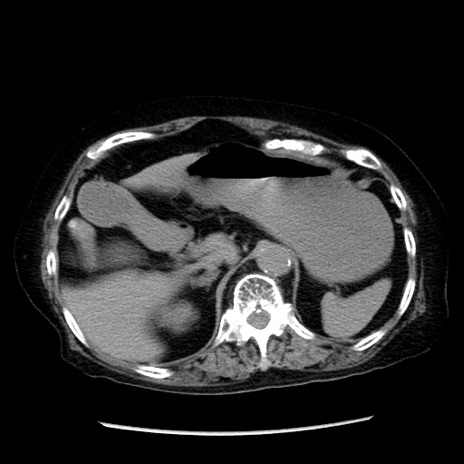

症例14(横断像)

症例

冠状断像

【症例】 90歳代女性

【主訴】 腹痛・嘔吐

【現病歴】今朝から左側腹部痛を認めた。 経過観察していたが、嘔吐を認めたため来院。

【既往歴】 子宮癌術後

【身体所見】 意識清明、BP 127/54mmHg、P 98bpm Sp02 95%(RA)、BT 35.8°C、腹部平坦・軟腸ぜん動音聴取良好、右下腹部圧痛(+) 反跳痛なし

【データ】WBC 9800、CRP 0.46